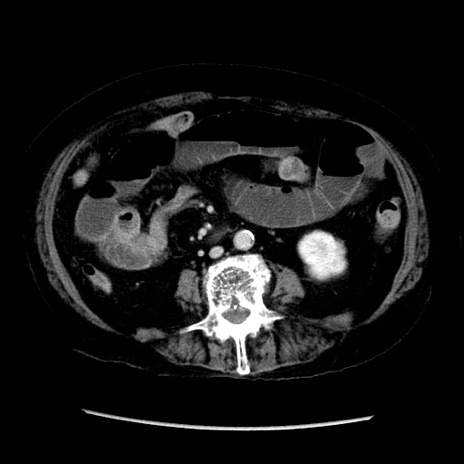

症例14(横断像)

【症例】 90歳代女性

【主訴】 腹痛・嘔吐

【現病歴】今朝から左側腹部痛を認めた。 経過観察していたが、嘔吐を認めたため来院。

【既往歴】 子宮癌術後

【身体所見】 意識清明、BP 127/54mmHg、P 98bpm Sp02 95%(RA)、BT 35.8°C、腹部平坦・軟腸ぜん動音聴取良好、右下腹部圧痛(+) 反跳痛なし

【データ】WBC 9800、CRP 0.46